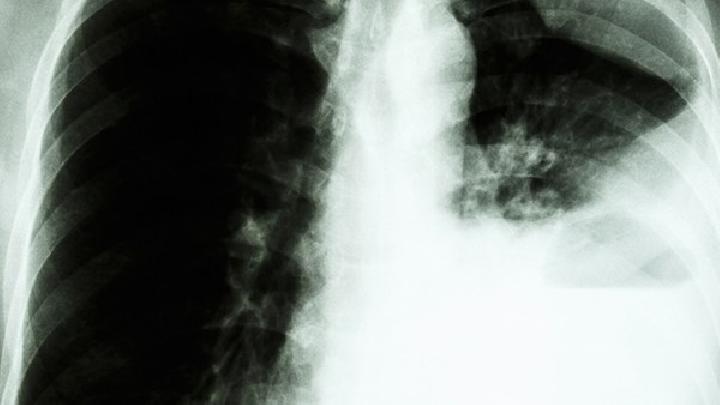

肺气肿是指终末细支气管远端的气道弹性减退,过度膨胀、充气和肺容积增大或同时伴有气道壁破坏的病理状态,按其发病原因肺气肿有老年性肺气肿、代偿性肺气肿、间质性肺气肿等几种类型,那么,肺气肿饮食要注意什么呢?